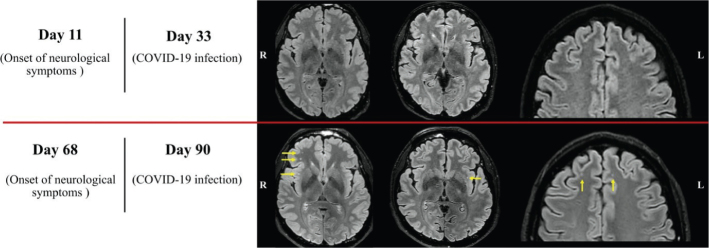

Results: Eleven days after the onset of neurological symptoms, DTI revealed early white matter changes, compared with HC, when standard MRI was normal. On day 68, DTI showed multiple white matter lesions compared with HC, visible at this time also by the MRI images, indicating inflammatory changes in different association and projection white matter pathways.